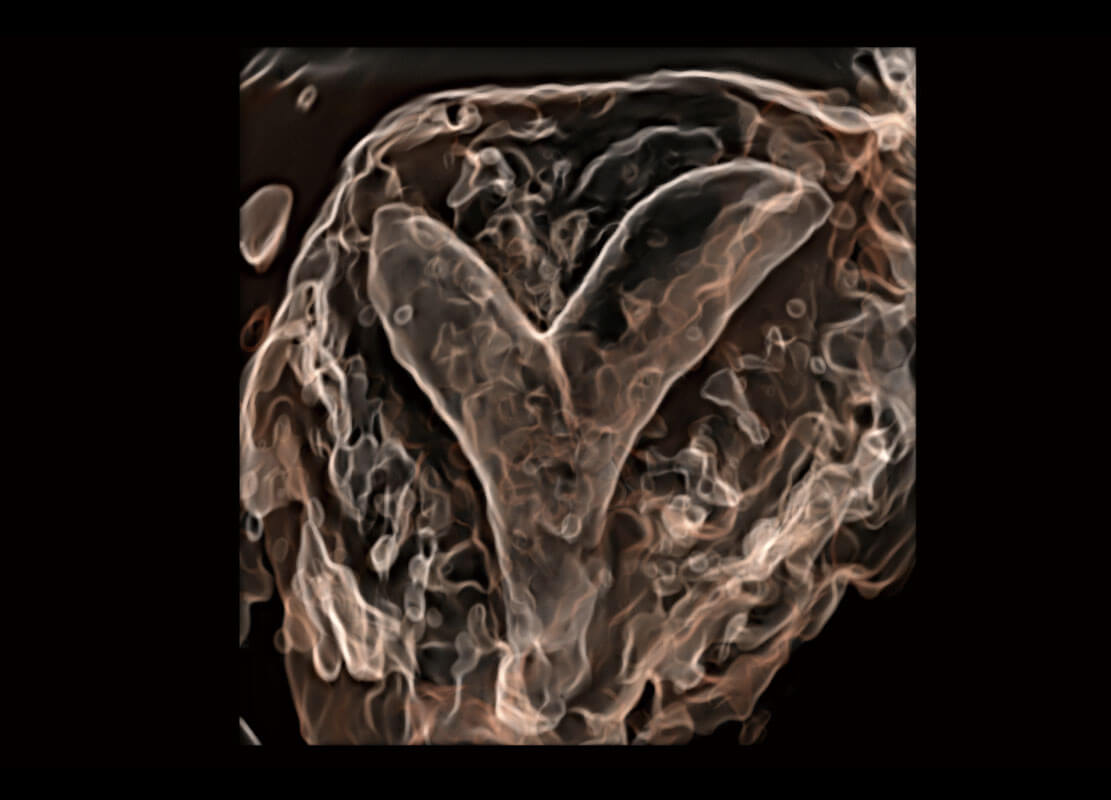

P60搭载一系列胎儿心脏成像技术,实现精细的胎儿心脏评估。

• 四腔切面

• 四腔心血流

• 右室双出口

• 胎心容积成像